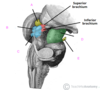

which of the following is the falx cerebri

A

B

C

D

E

which of the following is the falx cerebri

A

B

C

D

E

which of the following is the superior sagittal sinus?

A

B

C

D

E

which of the following is the superior sagittal sinus?

A

B

C

D

E

what is A?

infundibulum

falx cerebri

tentorium cerebelli

tentorial notch

falx cerebelli

what is A?

infundibulum

falx cerebri

tentorium cerebelli

tentorial notch

falx cerebelli